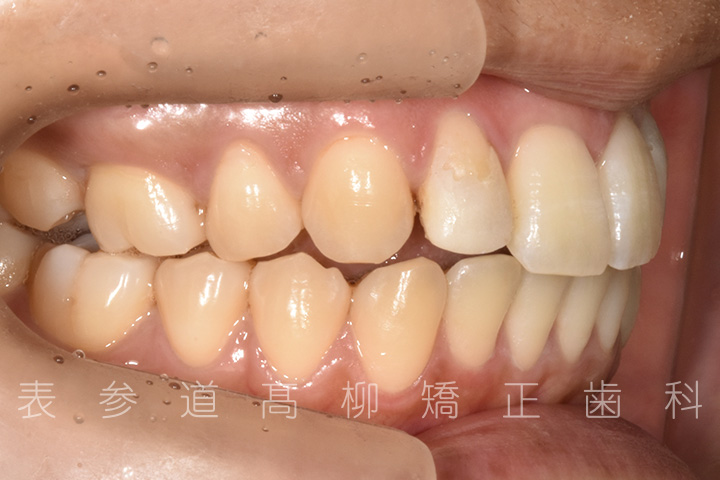

上の前歯が出ているのと前歯が小さいことをお悩みの患者様の症例をご紹介いたします。

・上顎前突(前歯の前方傾斜)

・2⏊2矮小歯(先天的に形態が小さい歯)

・上下前歯部叢生(凸凹歯並び)

術前術後の比較